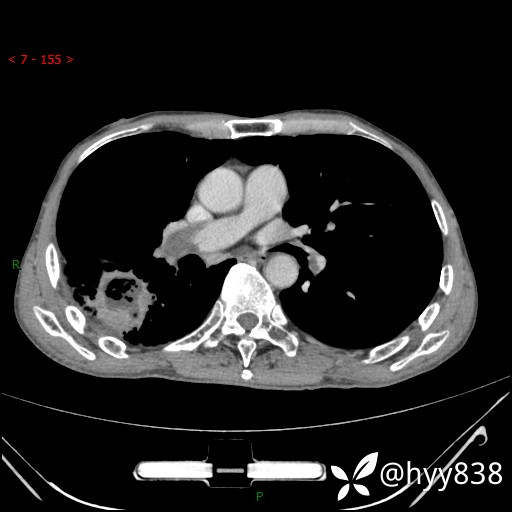

增强动脉期